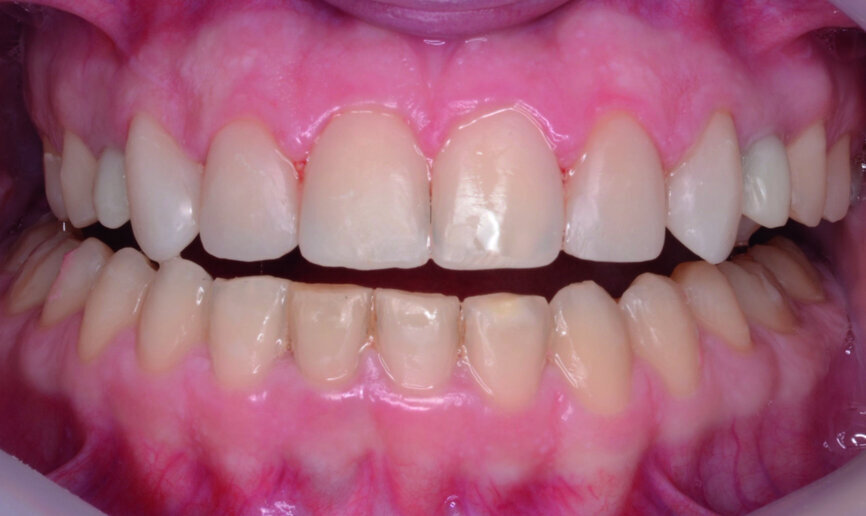

Then occlusal analysis (Figs. 11–21) was performed:

- Dental Class I.

- Insuficient overbite and overjet.

- Upper spacing due to the laterals agenesis (Fig. 18).

- Upper midline deviated to the right.

At the end of orthodontic treatment, gingival margins were well aligned, midlines were centred and canines and first premolars were positioned to facilitate the restorative phase of treatment (Figs. 34–36). At this phase, a final CR mounting and wax-up was performed (Figs. 37–39), as well as the anterior teeth restorations (Fig. 40).

Orthodontic treatment has improved both dental and facial aesthetics (Figs. 41–47) and the functionality of the occlusion (Figs. 48–52).